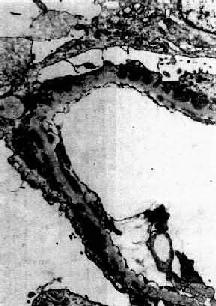

图12-19 膜性肾小球肾炎

电镜下见肾小球毛细血管基底膜增厚,电子致密沉积物被增生的基底膜包围并埋藏于基底膜内